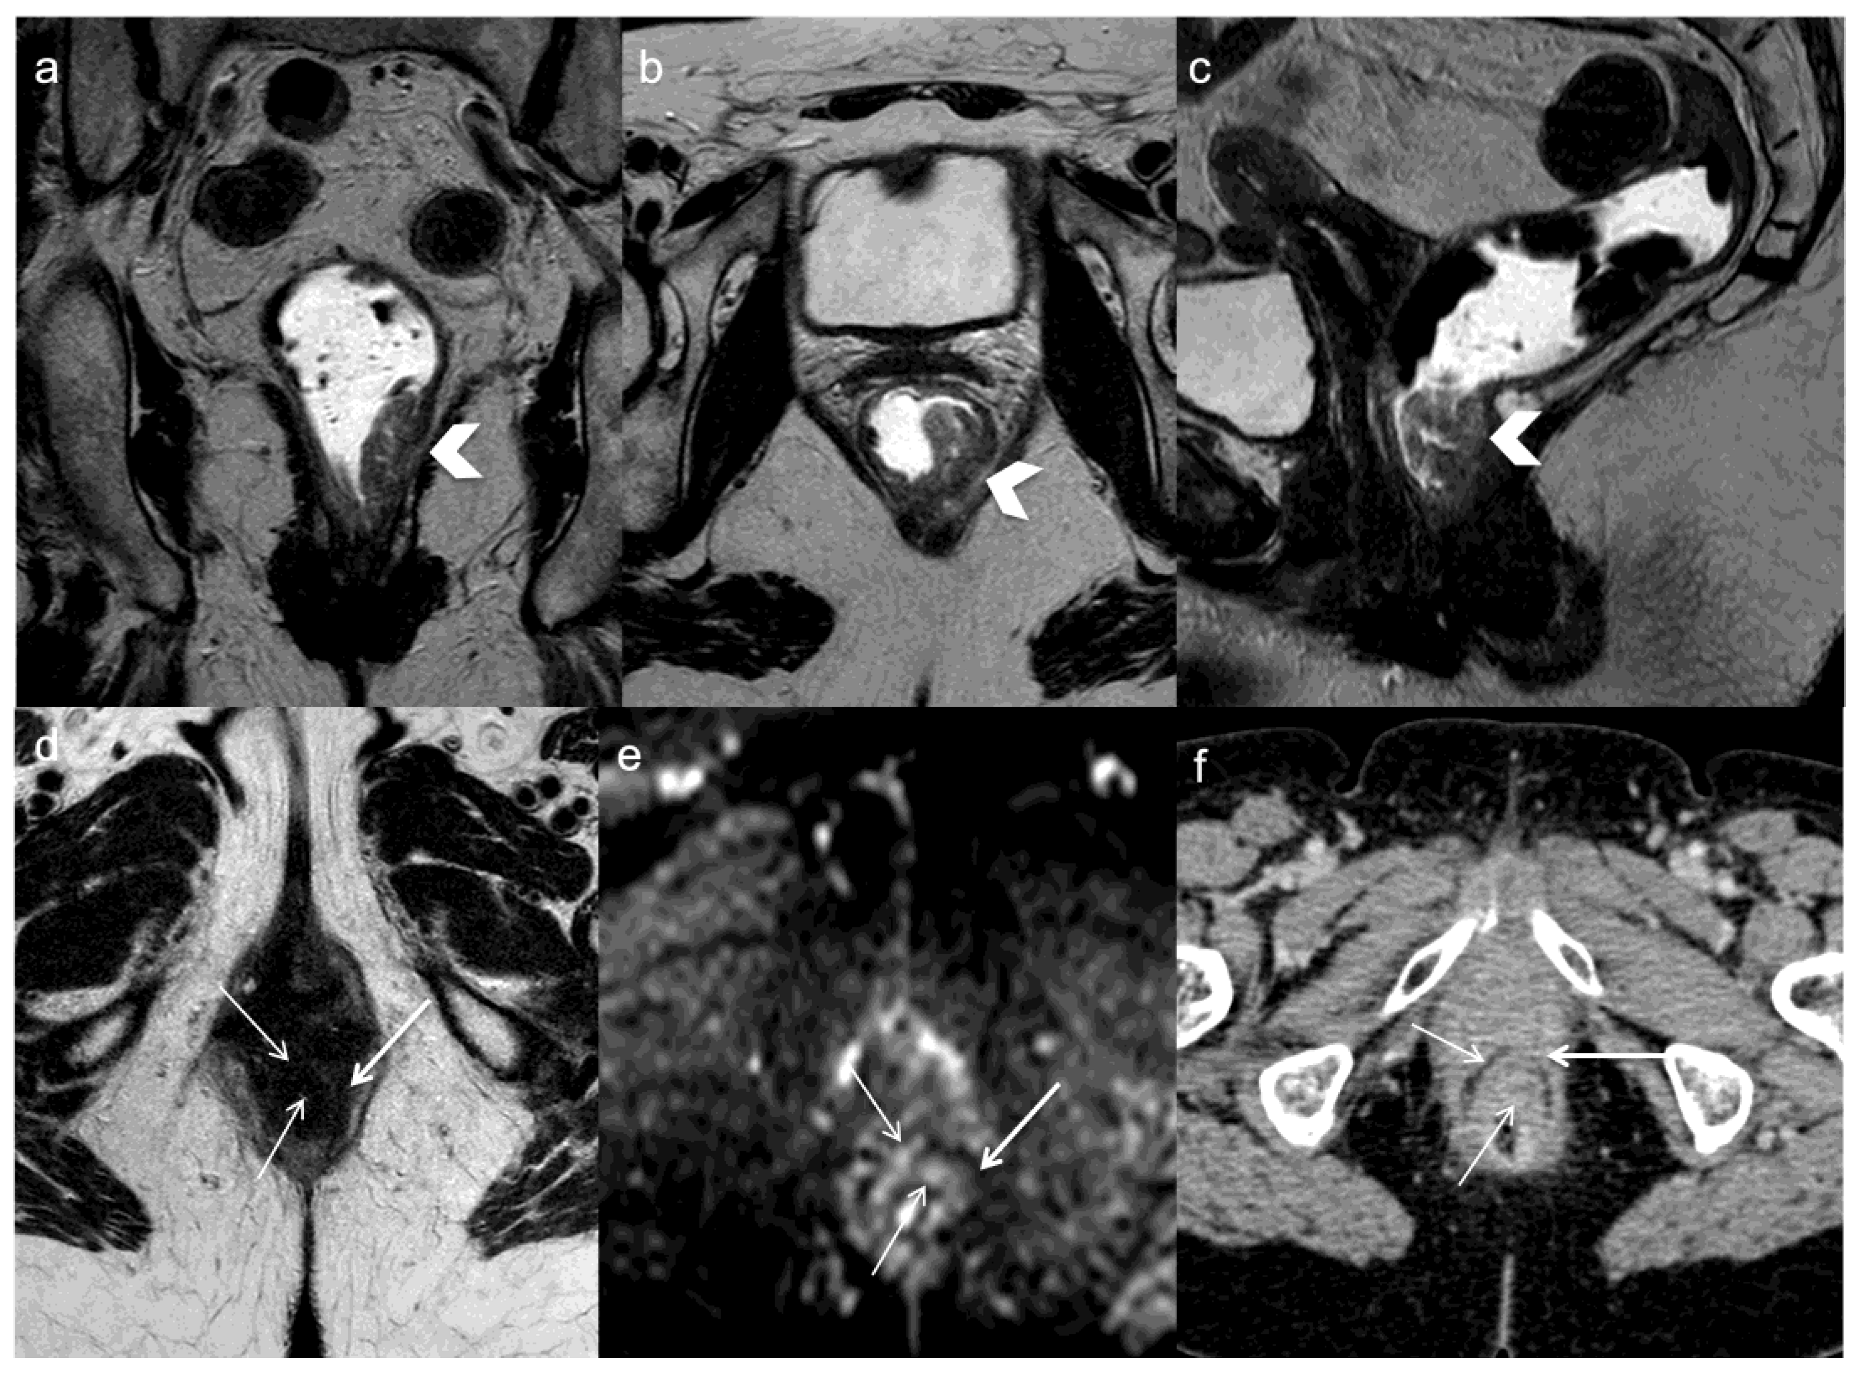

- Sinaei, M.; Swallow, C.; Milot, L.; Moghaddam, P.A.; Smith, A.; Atri, M. Patterns and Signal Intensity Characteristics of Pelvic Recurrence of Rectal Cancer at MR Imaging. Radiographics 2013, 33, E171–E187. [Google Scholar] [CrossRef]

- Dresen, R.C.; Kusters, M.; Daniels-Gooszen, A.W.; Cappendijk, V.C.; Nieuwenhuijzen, G.A.P.; Kessels, A.G.H.; Kessels, A.G.H.; de Bruïne, A.P.; Beets, G.L.; Rutten, H.J.T.; et al. Absence of tumor invasion into pelvic structures in locally recurrent rectal cancer: Prediction with preoperative MR imaging. Radiology 2010, 256, 143–150. [Google Scholar] [CrossRef]

- Messiou, C.; Chalmers, A.G.; Boyle, K.; Wilson, D.; Sagar, P. Pre-operative MR assessment of recurrent rectal cancer. Br. J. Radiol. 2008, 81, 468–473. [Google Scholar] [CrossRef]